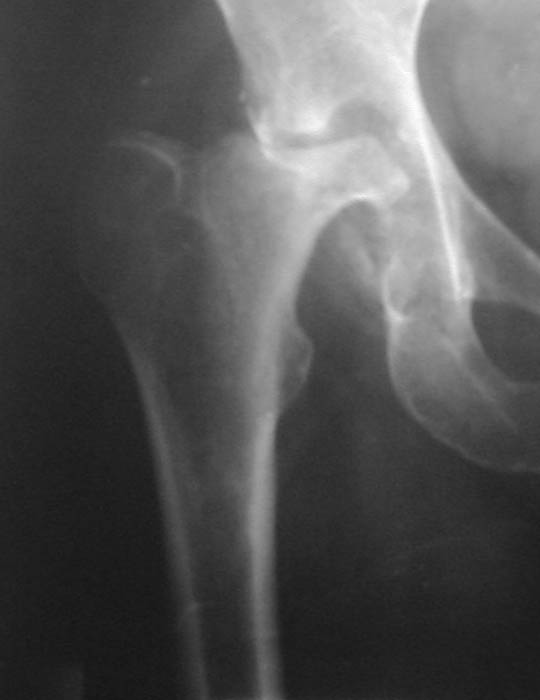

Уважаемые коллеги! Прошу Вас оказать консультативную помощь. Женщина, 44 года, инвалид 3 группы Диагноз: СКВ, асептический некроз головок обеих бедернных костей, двусторонний артроз 3-4 ст., болевой синдром, приводящая контрактура правого тазобедренного сустава,

хронический волчаночный гепатит, спленомегалия, анемия, СКВ с 2002 года (подтверждена наличием lupus-клеток), получала специфическую терапию, медрол 16 мг/сут. Боли в левом тазобедренном суставе появились в сентябре 2003 года. Динамика отражена на рентгенограммах. В марте 2004 года - синдром Мэллори-Вейса, кровотечение остановлено эндоскопически.

Ходит с тростью, хромота. Объем движений в суставах: справа - сгибание 90, разгибание 170, отведение 0, приведение 20, внутренняя ротация 15; слева - сгибание 90, разгибание 180, отведение 0, приведение 20, внутренняя ротация 0, наружная ротация 20.

Пациентка желает выполнить тотальное эндопротезирование. Допустимо ли выполнение подобной операции? При каких условиях, дополнительной терапии? Особые предоперационные мероприятия? Личный опыт? Комментарии? Мнения? Заранее благодарю!!!